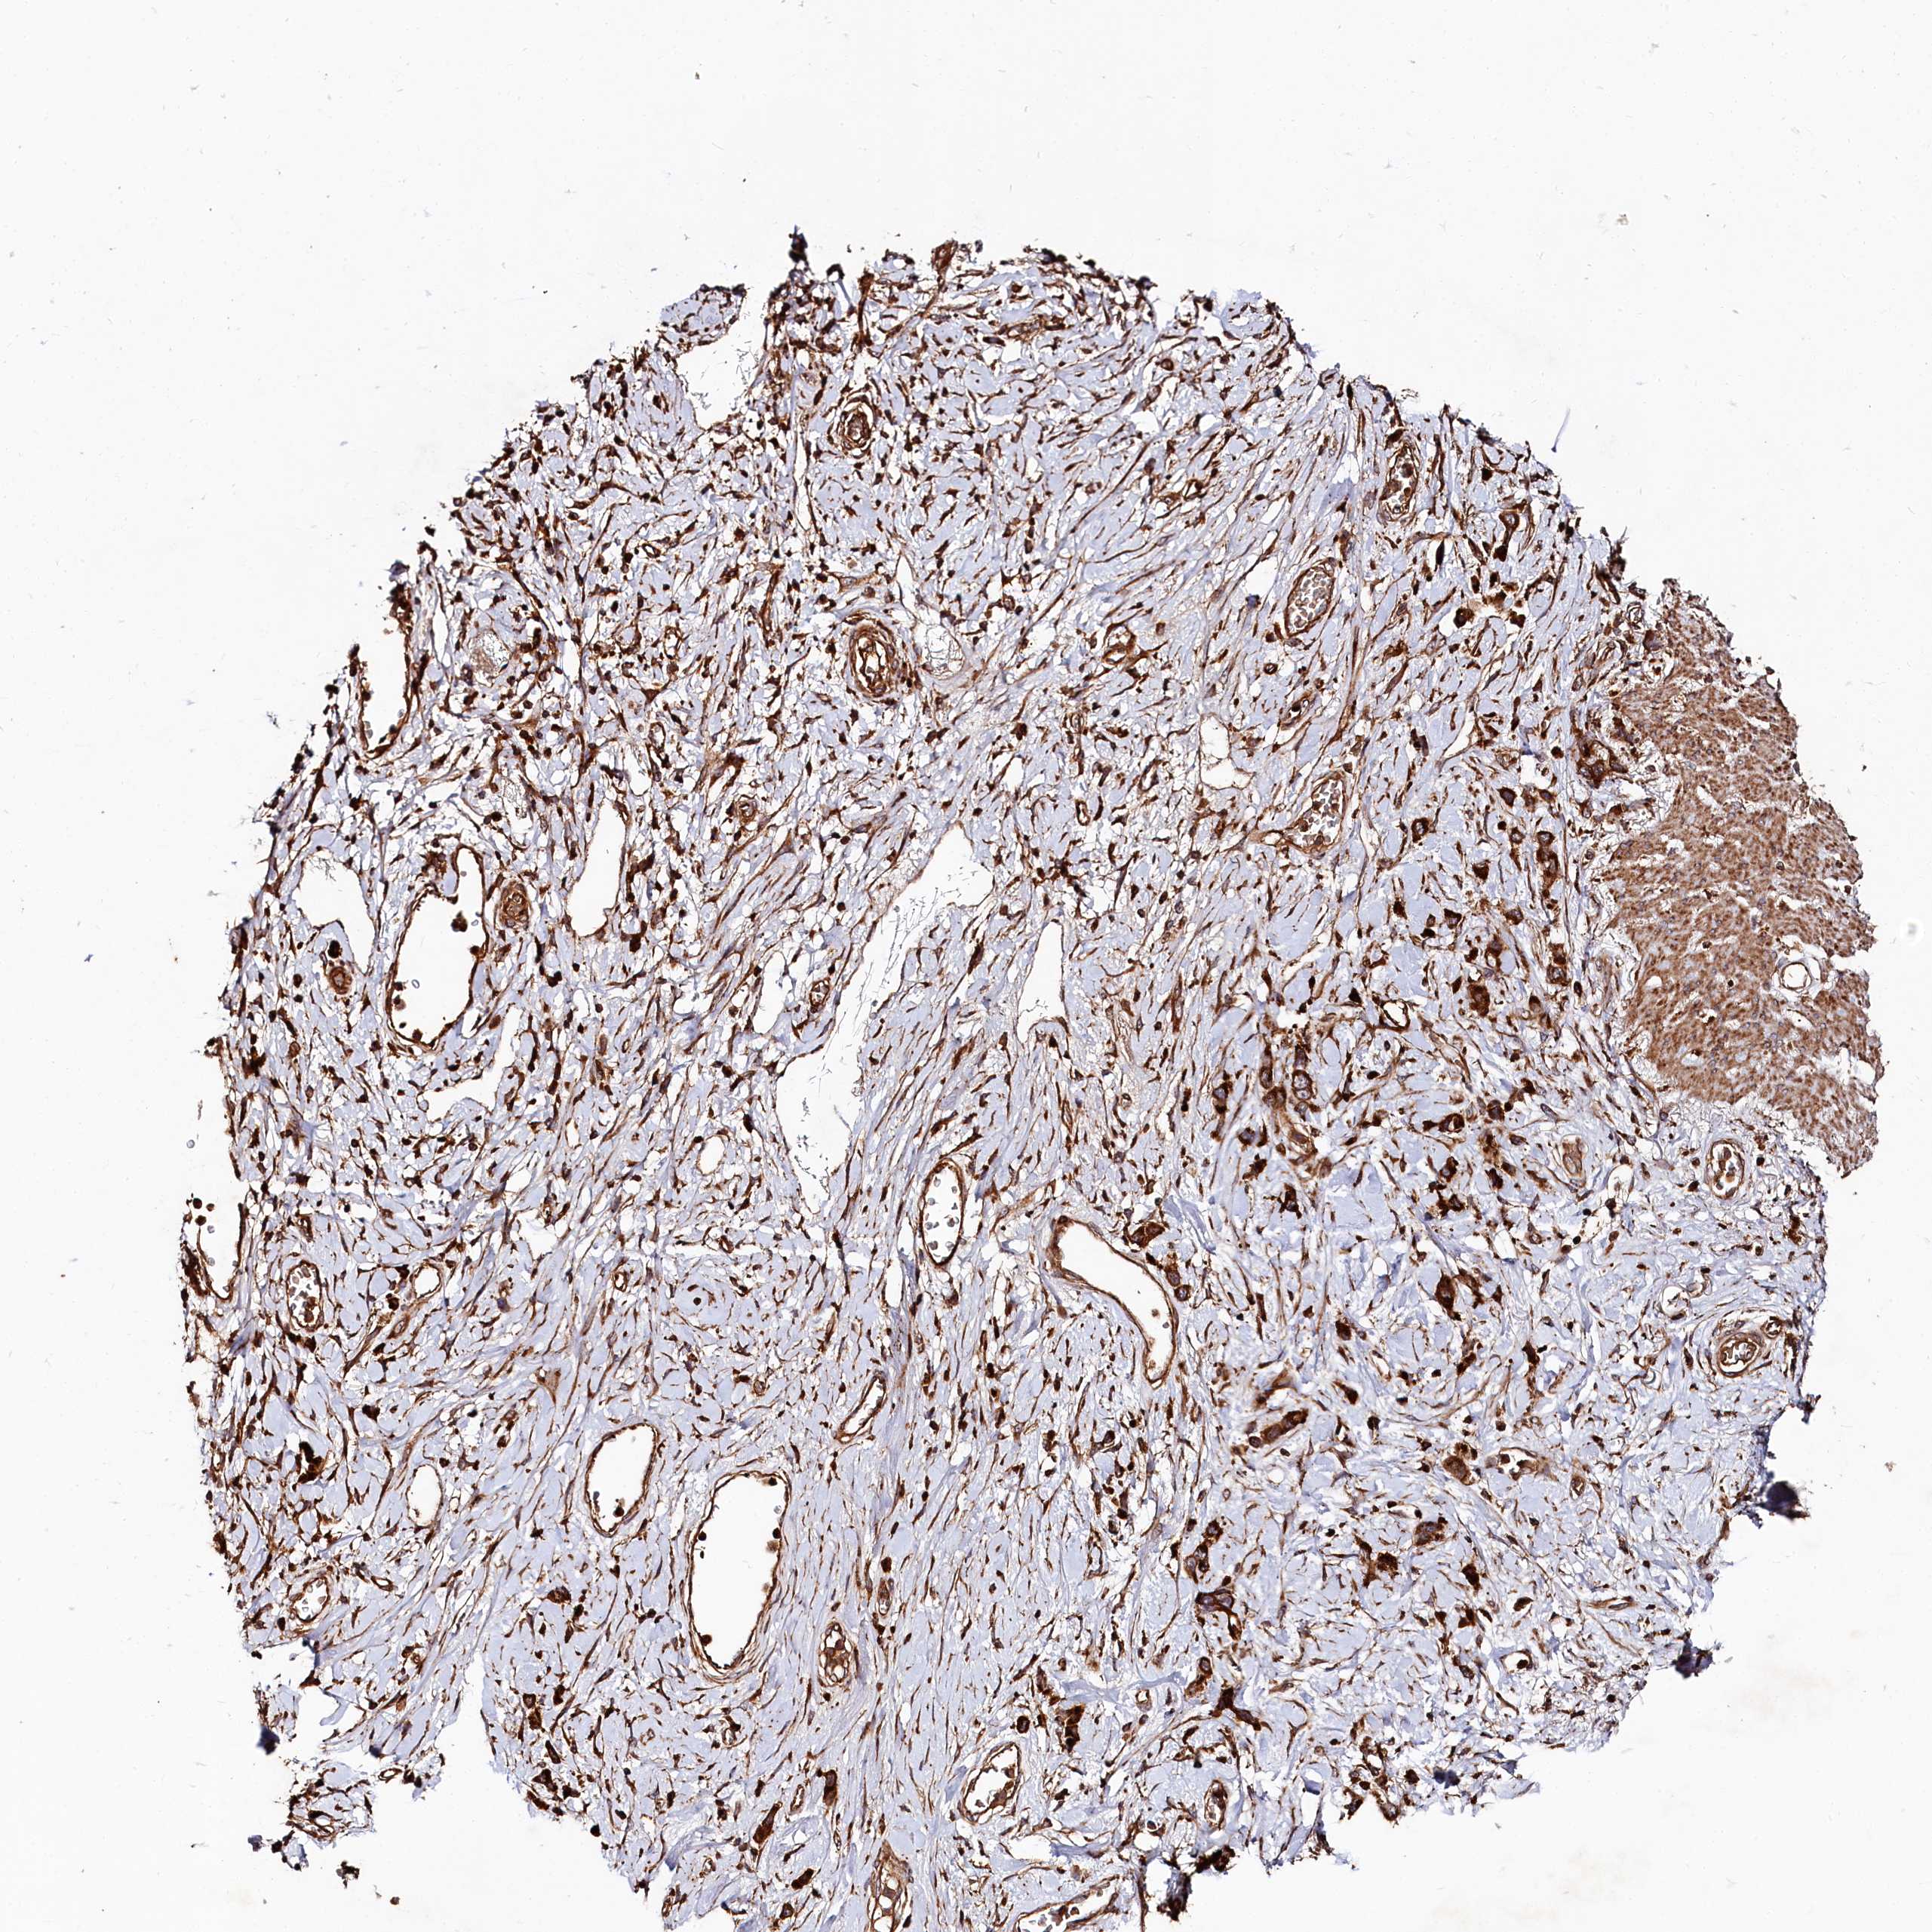

STOMACH CANCER - Protein expressioni

A mouse-over function shows sample information and annotation data. Click on an image to view it in a full screen mode. Samples can be filtered based on level of antibody staining by selecting one or several of the following categories: high, medium, low and not detected. The assay and annotation is described here.

Antibody stainingi

Antibody staining in the annotated cell types in the current human tissue is reported as not detected, low, medium, or high, based on conventional immunohistochemistry profiling in selected tissues. This score is based on the combination of the staining intensity and fraction of stained cells.

Each image is clickable and will lead to virtual microscopy that enables deeper exploration of all samples and also displays staining intensity scores, fraction scores and subcellular localization as well as patient and tissue information for each sample.

Antibody HPA039357

Staining

High

Medium

Low

Not detected

Intensity

Strong

Moderate

Weak

Negative

Quantity

>75%

75%-25%

<25%

None

Location

Nuclear

Cytoplasmic/membranous

Cytoplasmic/membranous,nuclear

Adenocarcinoma, NOS

Adenocarcinoma, High grade